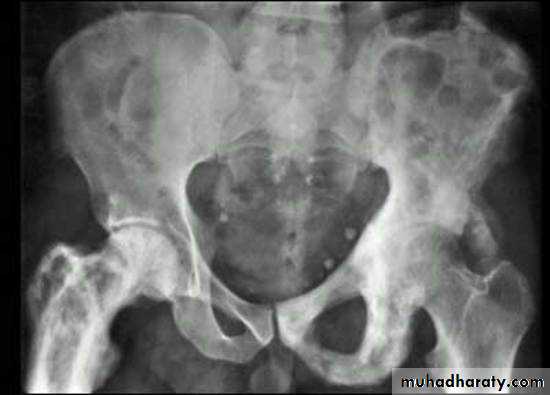

.bone deformity vertebral bodies are biconcave , the femora may be bowed & in severe cases the side walls of the pelvis may bend inwards , giving to the so called triradiate pelvis .

Hyperparathyroidism:

Excess parathyroid hormone secretion mobilizes calcium from the bones , resulting in a decrease in bone density , it may be primary from hyperplasia or tumour of the parathyroid glands or secondary to chronic renal failure. generalized loss of bone density.

. subperiosteal bone resorption.

. soft tissue calcification.

.brown tumour.